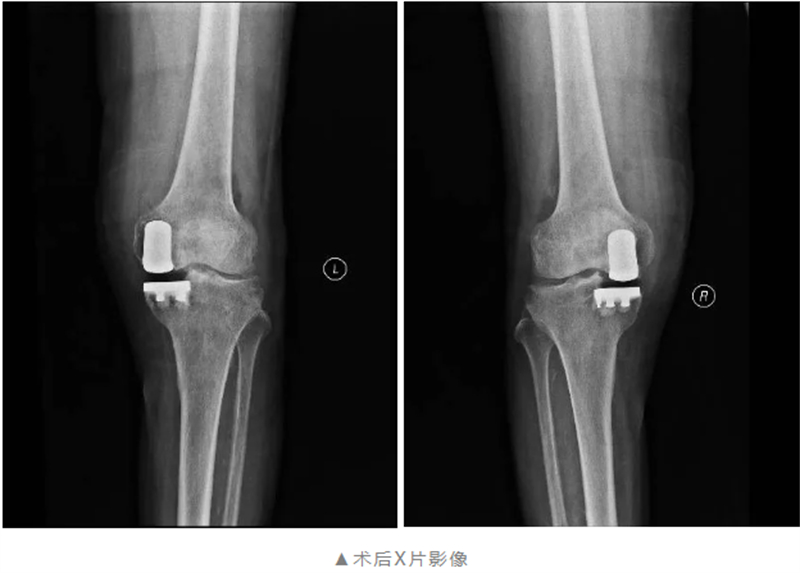

經過全面細致的檢查與多學科會診評估,關節(jié)骨病科團隊在與黃阿公及其家屬充分溝通后,制定了個性化的膝關節(jié)手術方案——雙側膝關節(jié)單髁置換術,在膝關節(jié)磨損的部位植入特殊材料的“墊片”,最大限度的保留了患者的本體感覺和關節(jié)功能。

經過術前的精心準備,術中麻醉科團隊的大力支持,關節(jié)骨病科團隊僅用不到2個小時就順利完成了雙側膝關節(jié)單髁置換術。術后在關節(jié)骨病科醫(yī)護團隊的精心護理與康復指導下,黃阿公雙膝關節(jié)痛感明顯減輕,膝關節(jié)功能逐步恢復,已能自主下床活動,被疾病折磨30余年終于重獲新生。